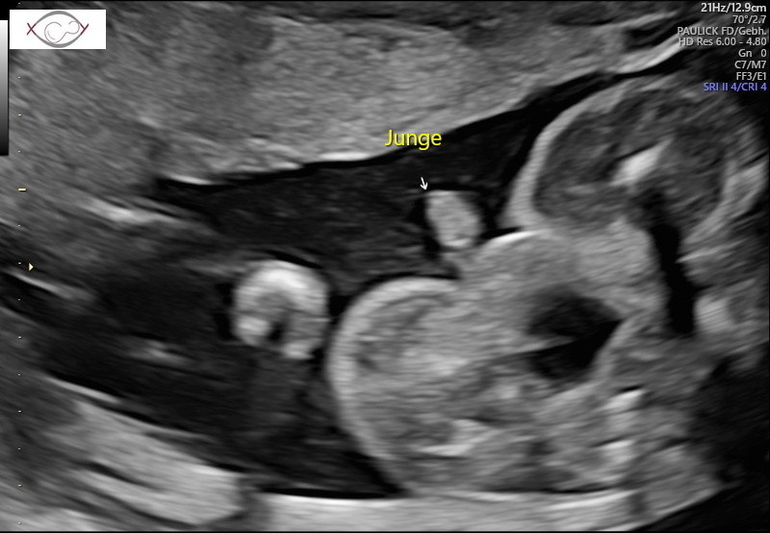

Теперь я особо ничего уже не боюсь👍 2,5 недели назад писала пост о не полном предлежании плаценты, она за это время поднялась и уже 2,5 см от зева🤗Ура, ура, ура🥳🥳🥳 Особо беременной себя до сих пор не чувствую, в том плане, что ни отёков, ни какого то дискомфорта пока не ощущаю, но жду, готовлюсь морально🤪. Для папы нашего сделали фото писюна, чтобы уж точно он уже был уверен, что мальчик😅🤣🤣🤣 Пяточку, которой малой мне пиночки отвешивает и личико попытались сфоткать, но скромняшка всё ручками закрывался.